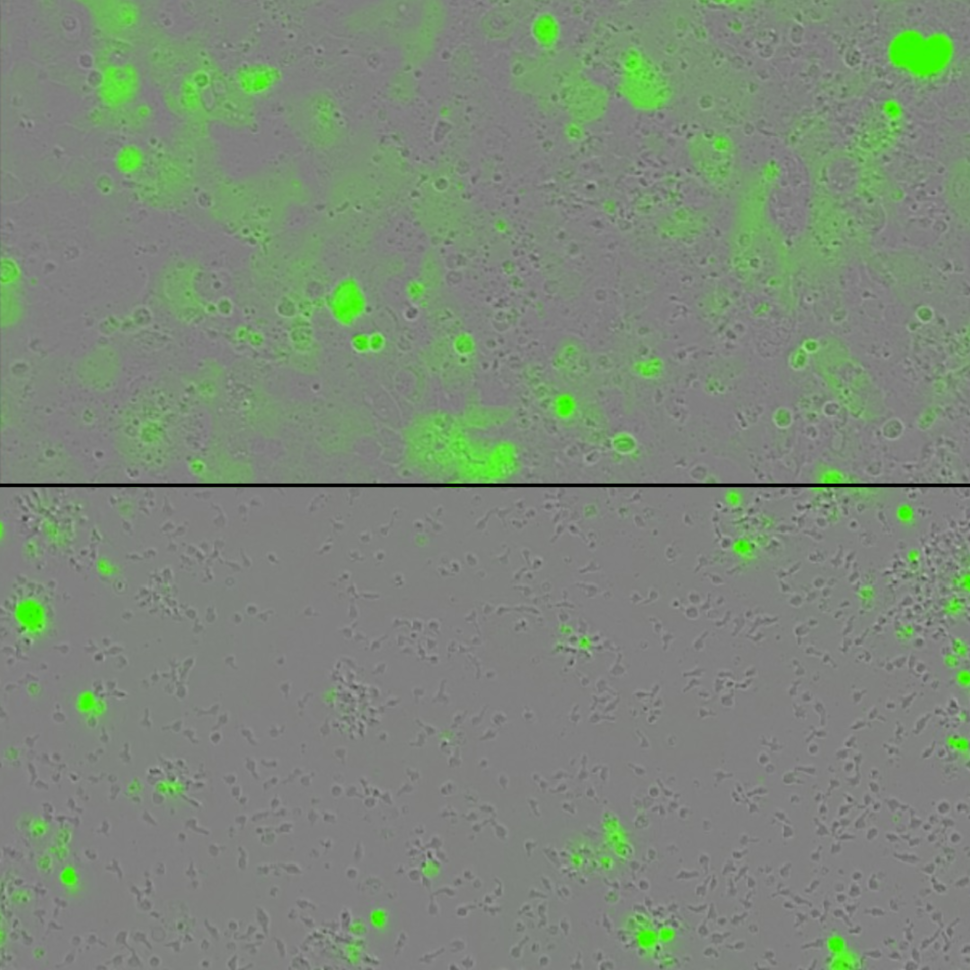

Tumor cells (green) are grown in a dish with engineered T cells alone (on the top) or with engineered T cells harboring two cytokines tethered to the surface (bottom image) . The engineered T cells containing the tethered cytokines lead to greater eradication of tumors.

Credit: Credit: Rosa Nguyen, National Cancer Institute

In laboratory studies, CAR and TCR T cells modified to express the cytokines IL-15 and IL-21 on their surface killed far more cancer cells than T cells carrying just one of these cytokines or neither of them. Previous research has found that treating patients with large amounts of cytokines caused severe, potentially fatal, side effects. The new approach aims to deliver this cytokine boost in a much more targeted way.